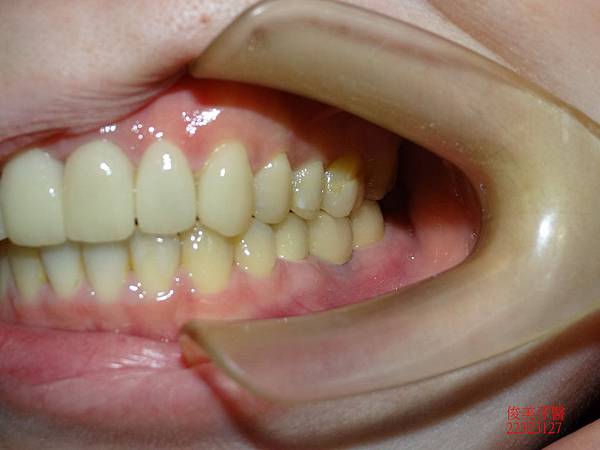

側邊咬合。

上排牙齒已有延長的現象,牙縫更容易塞東西,且沒有咀嚼功能。

療程結束後咬合良好。

牙縫不會直接嵌塞食物。